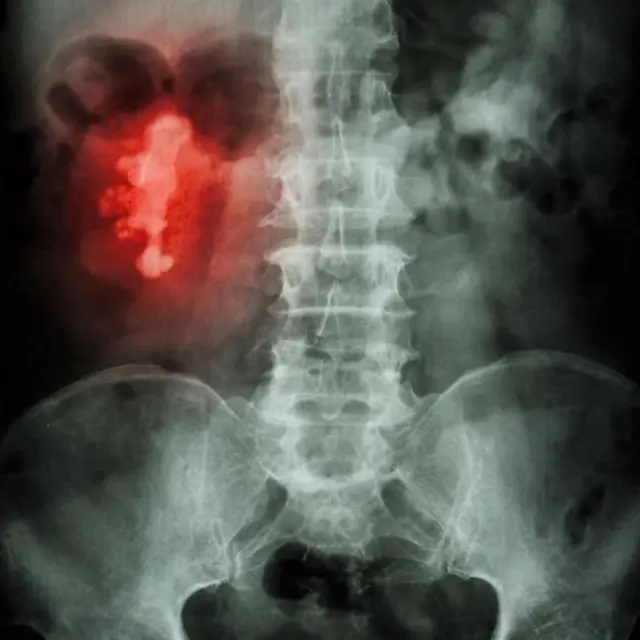

கற்கள் அசாதாரண வடிவத்திலும் இருக்கலாம். ஆனால் சிறுநீரக கால்வாயின் (calyces) கிளைகளுக்குள் கற்கள் உருவாகத் தொடங்கினால், அது மானின் கொம்பு வடிவத்தையும் பெறலாம். இது ஸ்டாக்ஹார்ன் கால்குலஸ் (staghorn calculus) என்று அழைக்கப்படுகிறது.